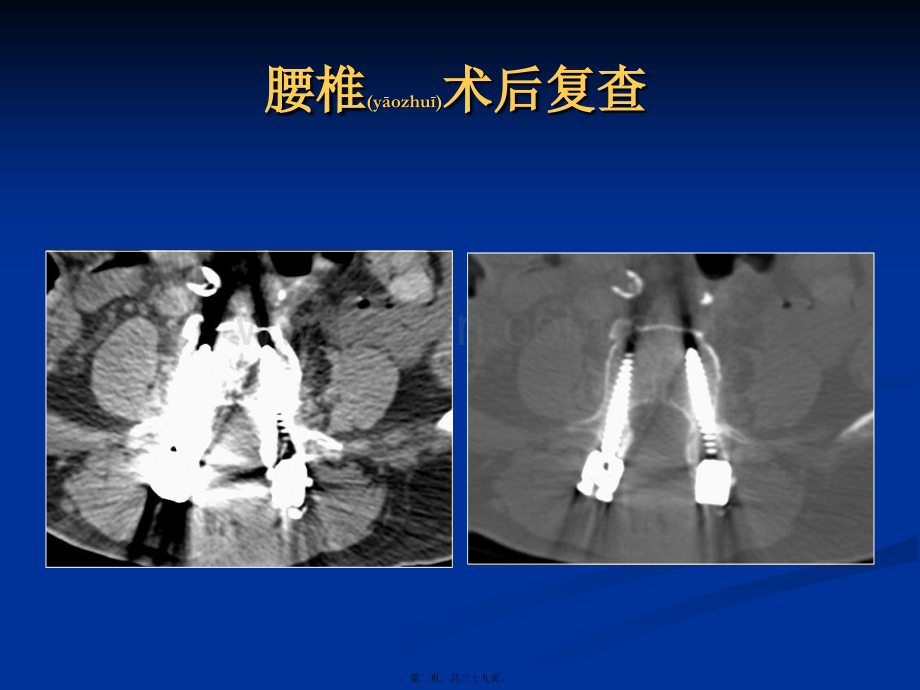

能谱能谱CT减除骨科金属减除骨科金属(jnsh(jnsh)植入植入物物伪影临床应用初探伪影临床应用初探王艳艳 2017-3-6第一页,共三十九页。腰椎腰椎(yozhu)(yozhu)术后复查术后复查第二页,共三十九页。腰椎腰椎(yozhu)(yozhu)术后重建术后重建第三页,共三十九页。临床临床(ln chun(ln chun)研究研究 能谱成像技术(能谱成像技术(能谱成像技术(能谱成像技术(GSIGSI)对减少骨科金属植入物伪影的)对减少骨科金属植入物伪影的)对减少骨科金属植入物伪影的)对减少骨科金属植入物伪影的 应用价值应用价值应用价值应用价值n n寻求寻求寻求寻求GSIGSI图像质量最佳的单能量成像点图像质量最佳的单能量成像点图像质量最佳的单能量成像点图像质量最佳的单能量成像点n n定量分析金属伪影对周围组织定量分析金属伪影对周围组织定量分析金属伪影对周围组织定量分析金属伪影对周围组织(z(z zh)zh)CTCT值及值及值及值及SDSD值的影响值的影响值的影响值的影响n n寻求最佳临床应用扫描条件寻求最佳临床应用扫描条件寻求最佳临床应用扫描条件寻求最佳临床应用扫描条件第四页,共三十九页。寻找最佳寻找最佳(zu ji)(zu ji)的单能量成像点的单能量成像点n n脊柱金属植入物患者脊柱金属植入物患者1919例例 n nGSIGSI能谱扫描后获得能谱扫描后获得(hud)(hud)能谱扫描数据能谱扫描数据 n n管电压管电压8080140 keV140 keV瞬时切换,切换时间为瞬时切换,切换时间为0.5 ms0.5 msn n管电流管电流600 mA600 mAn n螺距螺距0.9840.984:1 1n n层厚层厚0.625 mm0.625 mmn n矩阵矩阵512512512512第五页,共三十九页。寻找寻找(xnzh(xnzh o)o)最佳的单能量成像点最佳的单能量成像点 GSI Viewer软件进行后处理分析(fnx)(fnx)n n每隔每隔10 keV10 keV获得获得4040140 keV140 keV共共1111组单能量图像组单能量图像 n n层厚:层厚:0.625 mm 0.625 mm n n窗宽窗宽/窗位窗位 n n骨窗:骨窗:2000 HU/350 HU 2000 HU/350 HU n n软组织窗:软组织窗:400 HU/40 HU 400 HU/40 HU 第六页,共三十九页。40 50 60 70 80 90 100 110120 130 140140KVP不同(b tn)KeV和140KVP下软组织窗图像(400/40)第七页,共三十九页。40 50 60 70 80 90 100 110120 130 140 140KVP不同(b tn)KeV和140KVP下骨窗图像(2000/350)第八页,共三十九页。方法方法(fngf(fngf)n n典型(di(di nxng)nxng)层面选取:伪影最重层面(A)和无或少伪影层面(B)A B 第九页,共三十九页。实验实验(shyn)(shyn)方法方法n nCT值和SD值测定:n n1111组单能量组单能量(nngling)(nngling)图像图像A A、B B两个部位感兴趣区两个部位感兴趣区(ROI ROI)n n记录为记录为CT1CT1、CT2CT2和和SD1SD1、SD2SD2n n计算伪影处的金属伪影指数(AI)n n统计学分析第十页,共三十九页。结果结果(ji gu(ji gu)19例患者不同keV下A、B两个部位的CT值观察(gunch)指标如表 第十一页,共三十九页。结结 果果n n120 keV时,A、B两个部位间CT值差异无统计学意义(P0.05)n n表明(bi(bi omng)omng)伪影最重层面ROI的伪影已完全或接近全部消除n n明显优于混合能量图像 第十二页,共三十九页。结结 果果混合能量混合能量(nngling)(140 kvP)软组织窗和骨窗图像软组织窗和骨窗图像 120 keV软组织窗和软组织窗和骨窗图像骨窗图像 第十三页,共三十九页。结果结果(ji gu(ji gu)19例患者(hunzh)不同keV下A、B两个部位的AI值 如图第十四页,共三十九页。结结 果果n n不同keV下A、B两个部位的AI值n n4060 keV:n n两两比较,差异两两比较,差异(chy)(chy)均有统计学意义均有统计学意义(P P均均0.050.050.05)n n70 keV70 keV开始,伪影减除的比较明显开始,伪影减除的比较明显n n但较混合能量扫描时图像伪影较多但较混合能量扫描时图像伪影较多,不是图像质量不是图像质量最佳的单能量成像点最佳的单能量成像点 第十五页,共三十九页。青岛大学医学院附属青岛大学医学院附属(fsh)医院放射科医院放射科结果结果(ji gu(ji gu)上方上方(shn fn)为混合能量为混合能量(140 kvP)软组织窗和骨窗图像软组织窗和骨窗图像 下方为下方为70 keV软组织窗和骨窗图像软组织窗和骨窗图像第十六页,共三十九页。结结 论论n n120 keV120 keV为图像质量最佳为图像质量最佳(zu ji)(zu ji)的单能量成像点的单能量成像点n n 70 keV70 keV为伪影减除的分界点为伪影减除的分界点 n n120-140KeV 120-140KeV 移植物伪影减除效果最好移植物伪影减除效果最好第十七页,共三十九页。CASE 1120KVP 120KEV 120KEV+MARS软组织窗骨窗第十八页,共三十九页。CASE 2120KVP 120KEV 120KEV+MARS软组织窗 骨窗第十九页,共三十九页。CASE 3120KVP 120KEV 120KEV+MARS软组织窗骨窗MARS第二十页,共三十九页。大块大块(d kui)(d kui)金属植入物临床研究金属植入物临床研究n n探讨探讨 混合能量组、混合能量组、Mono组、组、MonoMARs(金属伪影消除重建(金属伪影消除重建(zhn(zhn jin)jin),Metal-Artifacts Reduction System)组伪影减除效果)组伪影减除效果第二十一页,共三十九页。大块金属大块金属(jnsh(jnsh)植入物临床研究植入物临床研究n n单侧或双侧髋关节置换术后:单侧或双侧髋关节置换术后:单侧或双侧髋关节置换术后:单侧或双侧髋关节置换术后:20112011年年年年4-74-7月患者月患者月患者月患者2121例例例例n n检查方法:螺旋检查方法:螺旋检查方法:螺旋检查方法:螺旋(luxun)(luxun)CTCT平扫,平扫,平扫,平扫,GEGE Discovery CT750 HDDiscovery CT750 HDn n扫描参数如下扫描参数如下扫描参数如下扫描参数如下:管管管管 电电电电 流:流:流:流:640mA640mA 管管管管 电电电电 压:压:压:压:140kVp140kVp 螺螺螺螺 距:距:距:距:0.9840.984:1 1 准直宽度:准直宽度:准直宽度:准直宽度:0.625640.62564 剂剂剂剂 量:量:量:量:25.53mGy25.53mGy 层层层层 厚:厚:厚:厚:0.625mm0.625mm 层层层层 间间间间 隔:隔:隔:隔:0.625mm0.625mm第二十二页,共三十九页。实验实验(shyn)(shyn)方法方法n nGSI ViewerGSI Viewer软件进行后处理分析软件进行后处理分析软件进行后处理分析软件进行后处理分析 每隔每隔每隔每隔10 keV10 keV获得获得获得获得4040140 keV140 keV共共共共1111组单能量图像组单能量图像组单能量图像组单能量图像(t xin(t xin)层层层层 厚:厚:厚:厚:0.625 mm0.625 mm 窗宽窗宽窗宽窗宽/窗位窗位窗位窗位 骨骨骨骨 窗:窗:窗:窗:2000 HU/350 HU 2000 HU/350 HU 软组织窗:软组织窗:软组织窗:软组织窗:400 HU/40 HU400 HU/40 HU 层面选择:选取金属伪影最重层面且伪影最重区域层面选择:选取金属伪影最重层面且伪影最重区域层面选择:选取金属伪影最重层面且伪影最重区域层面选择:选取金属伪影最重层面且伪影最重区域第二十三页,共三十九页。40keV50keV60keV70keV80keV90keV100keV110keV120keV130keV140keV40140keV不同不同(b tn)单能量组图像(软组织窗)单能量组图像(软组织窗)第二十四页,共三十九页。40keV50keV60keV70keV80keV90keV100keV110keV120keV130keV140keV40140keV不同不同(b tn)单能量组图像(骨单能量组图像(骨窗)窗)第二十五页,共三十九页。方法方法(fngf(fngf)n n层面选择:选取金属伪影最重层面且伪影最重区域层面选择:选取金属伪影最重层面且伪影最重区域层面选择:选取金属伪影最重层面且伪影最重区域层面选择:选取金属伪影最重层面且伪影最重区域n nROI ROI 选择:距金属边缘选取两个大小相同的兴趣区选择:距金属边缘选取两个大小相同的兴趣区选择:距金属边缘选取两个大小相同的兴趣区选择:距金属边缘选取两个大小相同的兴趣区n nCTCT值和值和值和值和SDSD值测定值测定值测定值测定 取上述取上述取上述取上述(shngsh)(shngsh)两个兴趣区两个兴趣区两个兴趣区两个兴趣区CTCT值和值和值和值和SDSD值的均值作为观察指标值的均值作为观察指标值的均值作为观察指标值的均值作为观察指标 n n统计学分析:采用统计学分析:采用统计学分析:采用统计学分析:采用SPSS17.0SPSS17.0统计软件处理数据统计软件处理数据统计软件处理数据统计软件处理数据 第二十六页,共三十九页。兴趣(xngq)(xngq)区选择示意图第二十七页,共三十九页。结果结果(ji gu(ji gu)n n主观评价:同时采用主观评价:同时采用主观评价:同时采用主观评价:同时采用MonoMono和和和和MarsMars技术处理的图像质量明技术处理的图像质量明技术处理的图像质量明技术处理的图像质量明 显高于常规显高于常规显高于常规显高于常规QCQC组,差异组,差异组,差异组,差异(chy)(chy)具有统计学意义具有统计学意义具有统计学意义具有统计学意义组别组别 病例病例1 12 23 34 45 56 67 78 89 9101011111212131314141515161617171818191920202121QCQC组组组组1 1分分分分1 1分分分分1 1分分分分1 1分分分分1 1分分分分1 1分分分分1 1分分分分1 1分分分分1 1分分分分1 1分分分分1 1分分分分1 1分分分分1 1分分分分1 1分分分分1 1分分分分1 1分分分分1 1分分分分1 1分分分分1 1分分分分1 1分分分分1 1分分分分MonoMono组组组组2 2分分分分2 2分分分分2 2分分分分2 2分分分分2 2分分分分2 2分分分分1 1分分分分2 2分分分分2 2分分分分2 2分分分分2 2分分分分2 2分分分分2 2分分分分2 2分分分分1 1分分分分2 2分分分分2 2分分分分2 2分分分分2 2分分分分2 2分分分分2 2分分分分MarsMars组组组组3 3分分分分3 3分分分分3 3分分分分3 3分分分分3 3分分分分3 3分分分分3 3分分分分3 3分分分分3 3分分分分3 3分分分分3 3分分分分3 3分分分分3 3分分分分3 3分分分分3 3分分分分3 3分分分分3 3分分分分3 3分分分分3 3分分分分3 3分分分分3 3分分分分表表1 21例髋关节置换术后例髋关节置换术后CT能谱成像组和常规能谱成像组和常规(chnggu)QC组图像质量评分结果组图像质量评分结果第二十八页,共三十九页。结果结果(ji gu(ji gu)n n量化分析量化分析(fnx)(fnx)CT值比较值比较 常规常规常规常规QCQC组和组和组和组和MonoMonoMarsMars组组组组CTCT值的差异具有统计值的差异具有统计值的差异具有统计值的差异具有统计 学意义(学意义(学意义(学意义(t t 3.2983.298,P P0.050.05)MonoMono组和组和组和组和MonoMonoMarsMars组组组组CTCT值的差异具有统计学值的差异具有统计学值的差异具有统计学值的差异具有统计学 意义(意义(意义(意义(t t 2.9832.983,P P0.050.05)第二十九页,共三十九页。结果结果(ji gu(ji gu)n n量化分析量化分析 SD值比较值比较(b(b jio)jio)常规常规常规常规QCQC组和组和组和组和MonoMonoMarsMars组组组组SDSD值的差异具有统计值的差异具有统计值的差异具有统计值的差异具有统计 学意义(学意义(学意义(学意义(t t 3.4653.465,P P0.050.05)MonoMono组和组和组和组和MonoMonoMarsMars组组组组SDSD值的差异具有统计学值的差异具有统计学值的差异具有统计学值的差异具有统计学 意义(意义(意义(意义(t 3.7823.782,P P0.050.05)第三十页,共三十九页。结结 论论n nGSIGSI能谱成像技术能谱成像技术能谱成像技术能谱成像技术(jsh)(jsh)能有效减除术后金属植入伪影,能有效减除术后金属植入伪影,能有效减除术后金属植入伪影,能有效减除术后金属植入伪影,图像质量明显提高图像质量明显提高图像质量明显提高图像质量明显提高n n观察髋关节置换术后图像最佳观察髋关节置换术后图像最佳观察髋关节置换术后图像最佳观察髋关节置换术后图像最佳keVkeV是是是是120120140keV140keVn nMonoMonoMarsMars组减除伪影效果明显组减除伪影效果明显组减除伪影效果明显组减除伪影效果明显n nMARsMARs技术在减除金属伪影的同时,使金属植入物形技术在减除金属伪影的同时,使金属植入物形技术在减除金属伪影的同时,使金属植入物形技术在减除金属伪影的同时,使金属植入物形态发生轻微改变态发生轻微改变态发生轻微改变态发生轻微改变第三十一页,共三十九页。病例病例(bngl)(bngl)1 M/65Y 右髋关节置换术后半年右髋关节置换术后半年ABQC 组组 图图 像像Mars 组组 图图 像像第三十二页,共三十九页。病例病例(bngl)(bngl)2 M/52Y 右髋关节置换术后右髋关节置换术后1月月QC 组组 图图 像像 140keVMono 组组 图图 像像 140keVMars 组组 图图 像像第三十三页,共三十九页。病例病例(bngl)(bngl)3 F/24Y 左髋关节置换术后左髋关节置换术后2月月QC 组组 图图 像像 140keVMars 组组 图图 像像 140keVMono 组组 图图 像像 第三十四页,共三十九页。病例病例(bngl)(bngl)4 M/41Y 双髋关节置换术后双髋关节置换术后1月月QC 组组 图图 像像 140keV Mars组图像组图像(t xin)140keV Mono组图像组图像(t xin)第三十五页,共三十九页。病例病例(bngl)(bngl)4 M/41Y 双髋关节置换术后双髋关节置换术后1月月QC 组组 图图 像像 140keVMars 组组 图图 像像 140keVMono 组组 图图 像像 第三十六页,共三十九页。病例病例(bngl)(bngl)5 M/81Y 右膝关节置换术后右膝关节置换术后11月月 140kVpQC 组组 图图 像像 140keVMars 组组 图图 像像第三十七页,共三十九页。临床临床(ln chun(ln chun)应用应用n n120-140KeV 植入物伪影减除(ji(ji n ch)n ch)效果最好n n小块移植物:n nMono Mono,不加,不加MARsMARsn n大块移植物:n nMonoMonoMARsMARs第三十八页,共三十九页。内容(nirng)总结能谱CT减除骨科金属植入物伪影临床应用初探。王艳艳 2017-3-6。GSI能谱扫描后获得能谱扫描数据(shj)。管电压80140 keV瞬时切换,切换时间为0.5 ms。每隔10 keV获得40140 keV共11组单能量图像。11组单能量图像A、B两个部位感兴趣区(ROI)。记录为CT1、CT2和SD1、SD2。两两比较,差异均无统计学意义(P均0.05)。软组织窗:400 HU/40 HU第三十九页,共三十九页。